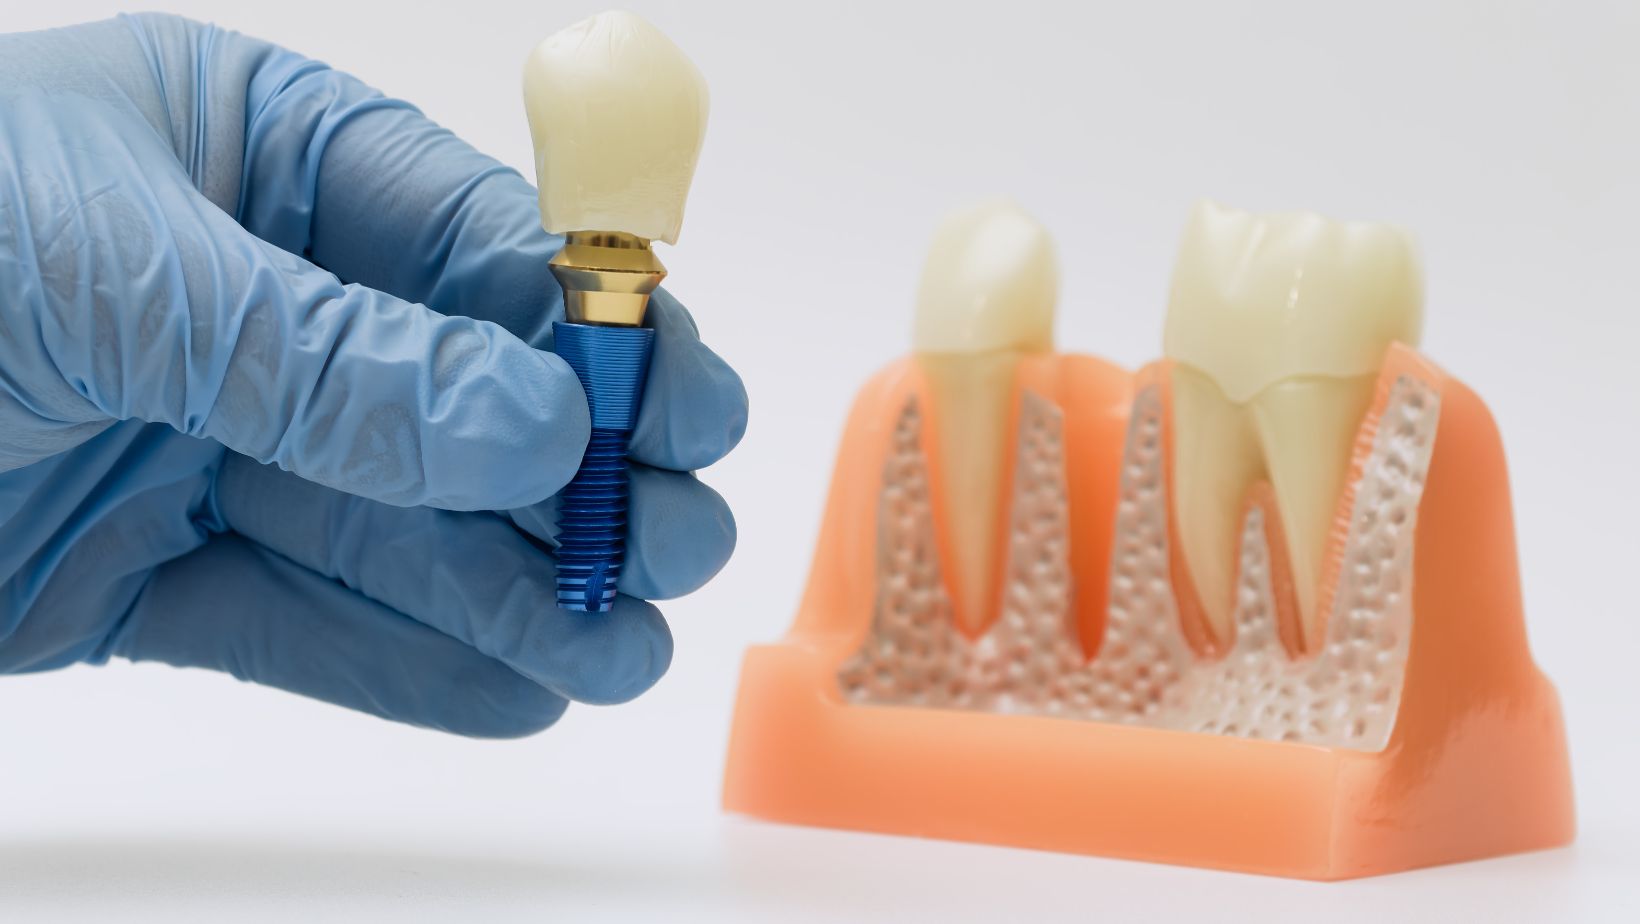

Dental implants are titanium posts surgically placed into your jawbone to replace tooth roots. After healing, they fuse with bone (osseointegration) and provide a stable anchor for single crowns, bridges, or full-arch prostheses like All‑on‑4.

You can expect multiple visits: implant placement, a healing period of weeks to months, then attachment of the final restoration. Implants preserve jawbone by transmitting chewing forces to bone, which helps prevent the bone loss that follows tooth extraction.